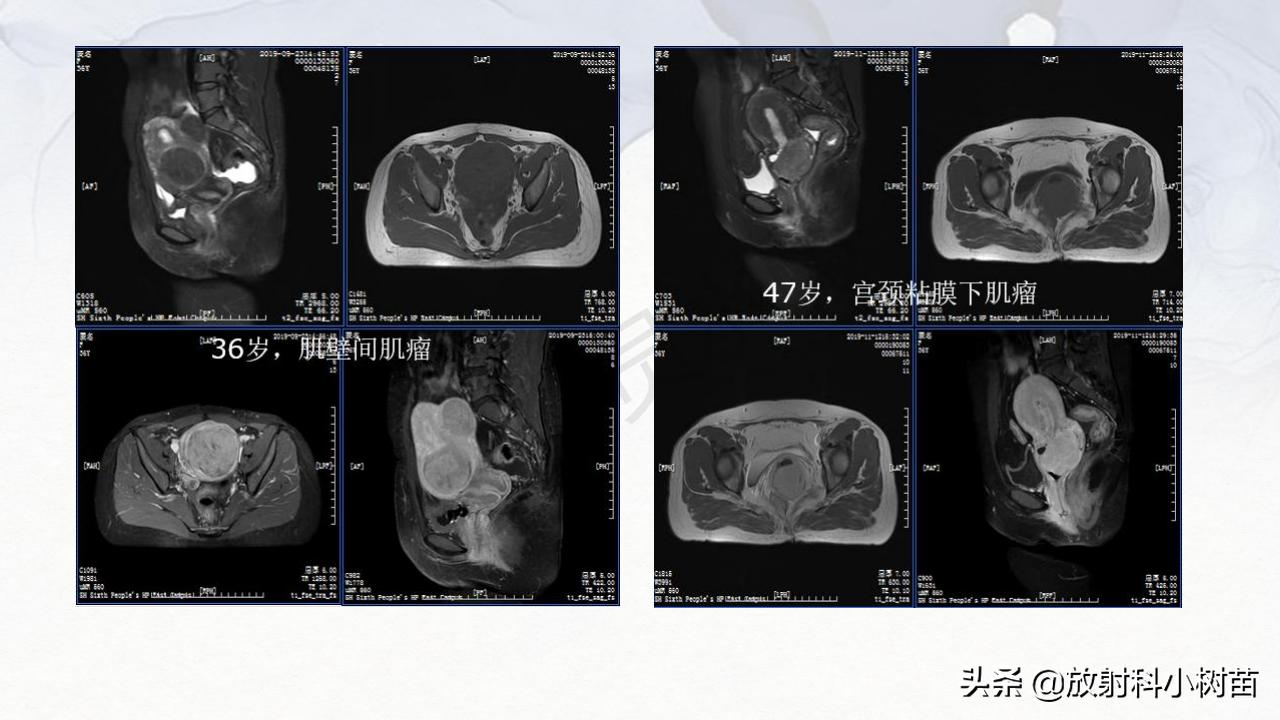

子宫体:肌层?(腺肌症,肌瘤,肉瘤),内膜?(增生,息肉、内膜癌)

宫颈:(息肉,囊肿,肌瘤,内膜癌)